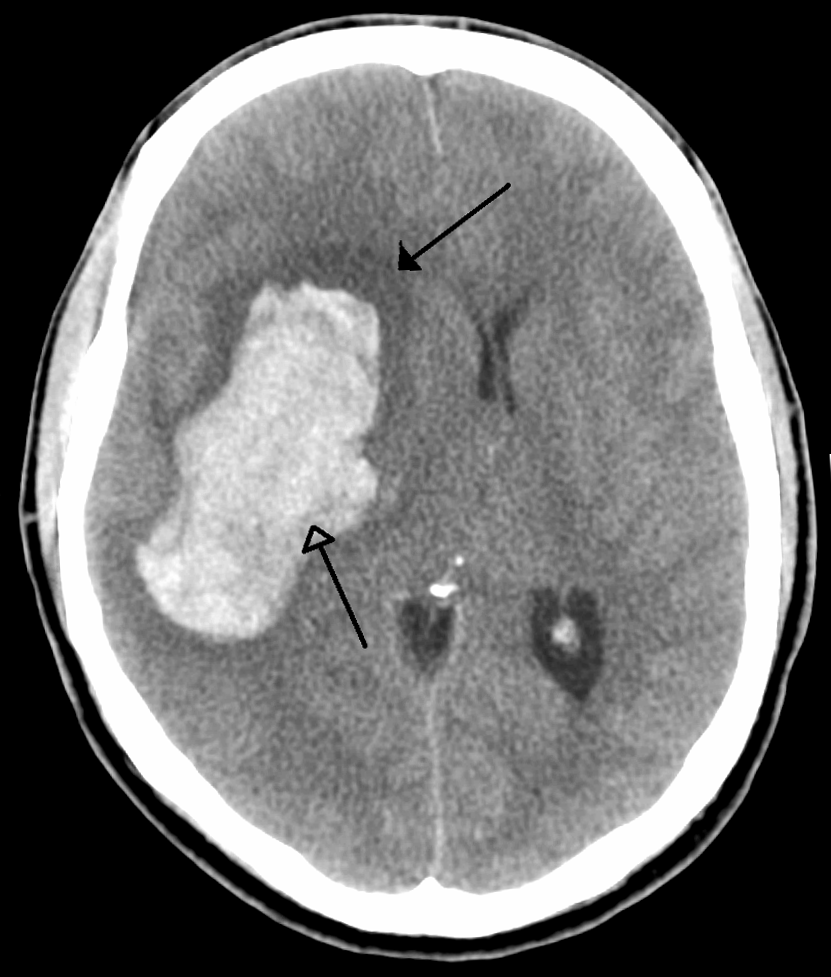

Example 3

Diagnosis

Subarachnoid Haemorrhage